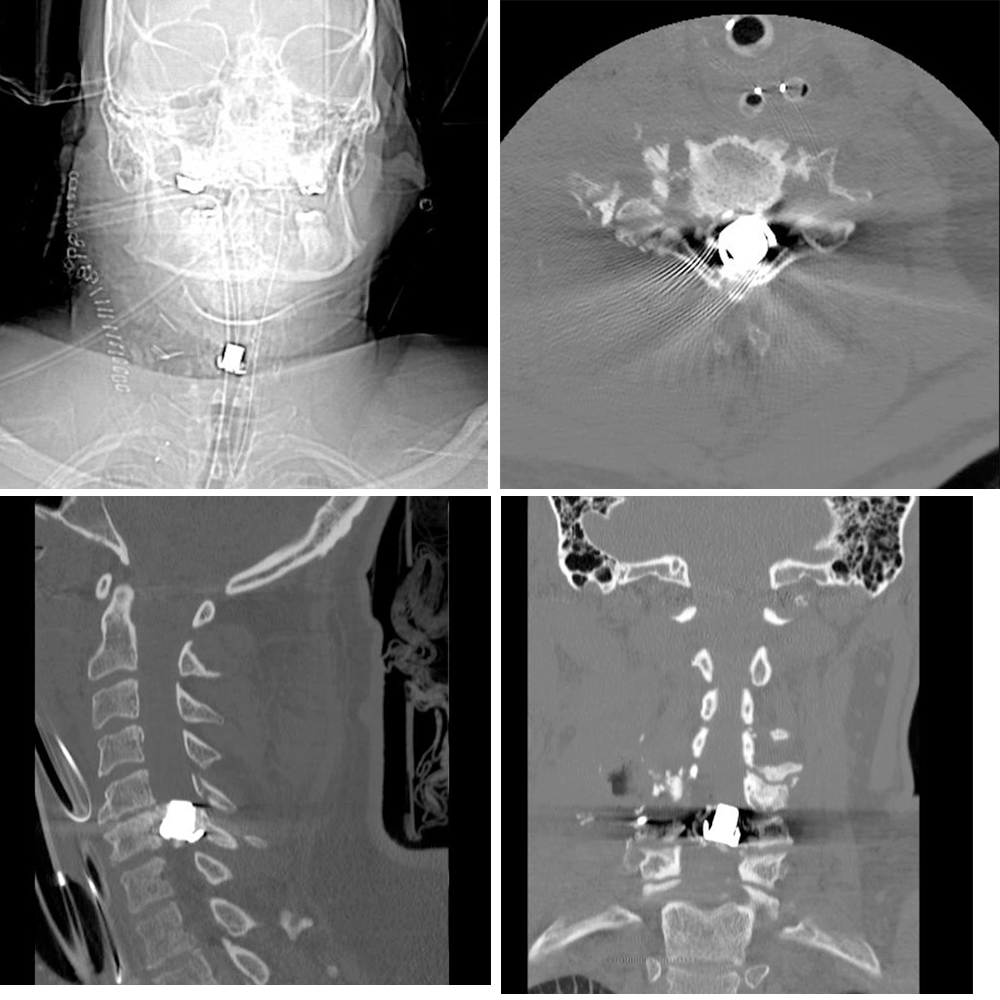

Post-angiography and embolization, the patient was sent for a computer tomography (CT) scan for completion imaging. The radiopaque bullet appeared to occupy most of the spinal canal at the level of C6. Fractures were appreciated at C6 with a comminuted fracture of the vertebral body, C7 with a non-displaced fracture of the vertebral body, and C4/C5 with a fracture of the right transverse processes and foramen (Figure 2).

Figure 2. Radiopaque Bullet Occupying Most of Spinal Canal at C6 Level. Published With Permission

C7 non-displaced fracture, extensive comminuted fracture of C6 vertebra, and fracture of right lateral aspect of C5 vertebra involving C4 right transverse process and foramen.

The patient required blood, intravenous fluids, and vasopressors to maintain hemodynamic stability in the settings of acute hemorrhagic and neurogenic shock. He was maintained on ventilator support for the next few days with subsequent clinical stabilization and surgical fixation of his cervical spine by neurosurgery on postoperative day 4 using an anterior approach (Figure 3). The decision was made to leave the retained bullet to minimize potential damage during retrieval.

Figure 3. Stabilization of Cervical Spine. Published With Permission